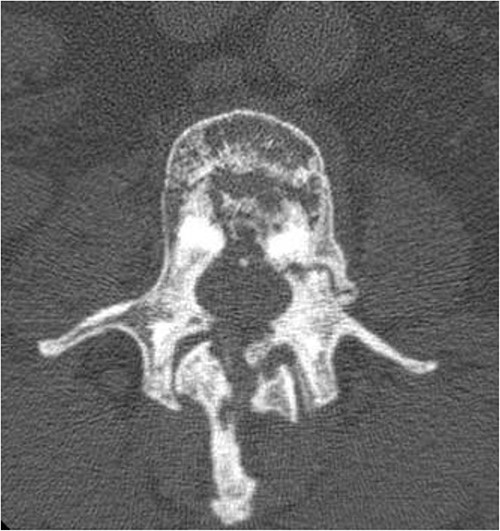

Six months later, he complained about lumbar pain which irradiated into the right thigh and knee. A CT scan of the lumbar spine showed multiple lumbar spine stress fractures, and CT myelography showed complete obstruction at L2–3 level (Figs 4 and 5). Conservative therapy was ineffective. Therefore, the patient was transferred to a spinal center. There he underwent L2–L3 decompression with short-term effect because decompression resulted in instability. 360° spondylodesis was done; however, it resulted in non-union, and the material was removed (Fig. 6).

Sagittal view of CT lumbar spine myelography. Note also the density of sclerotic bone.